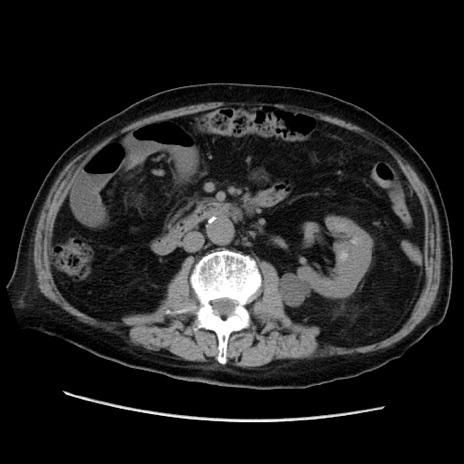

症例21(横断像)

【症例】70歳代男性

【主訴】腹痛

【現病歴】肝硬変・肝細胞癌にてかかりつけの方。約9時間前に食後より腹痛出現。症状が徐々に増悪し、嘔吐出現したため来院。

【既往歴】肝硬変、肝細胞癌(RFA、TACE後)

【身体所見】意識清明、表情苦悶様、BT 36℃、BP 129/78mmHg、P 88bpm、SpO2 97%(RA)、右上腹部から心窩部にかけて圧痛あり、反跳痛なし、筋性防御あり。

【データ】WBC 5800、CRP 0.16